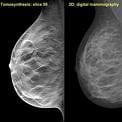

August 6, 2009 - The use of digital breast tomosynthesis and full-field digital mammography (FFDM) combined may be associated with a substantial decrease in recall rate, according to a study performed at UPMC in Pittsburgh, Penn., published in the American Roentgen Ray Society.

An estimated 10 percent of women in the United States are recalled for a second mammogram after an abnormality is detected on the first one. Some researchers believe that digital breast tomosynthesis depicts the breast tissue in a way which may allow radiologists to identify some tumors which could be missed with standard two-dimensional mammography.

In the study, 125 patients were evaluated using a combined method of digital breast tomosynthesis and standard digital mammography. The use of digital breast tomosynthesis and FFDM was associated with a 30 percent reduction in recall rate for cancer-free examinations that would have led to recall if FFDM had been used alone, reported Jules H. Sumkin, M.D., one of the authors of the study.